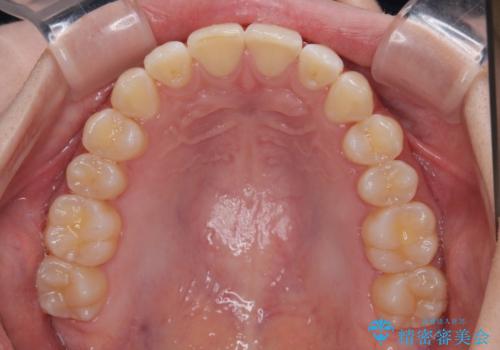

- 上下前歯の重なりを気にして来院された患者様です。

安価なインビザラインパッケージを用いての治療を希望されており、デコボコの程度が中等度であったため、インビザライン・モデレートを用いて矯正治療を行うこととしました。

インビザライン・モデレートは、製作できるアライナーの枚数に制限があるため、移動可能な量に限りがあるものの、インビザライン・ライトよりも枚数が多いため、幅広い症例に対応可能です。